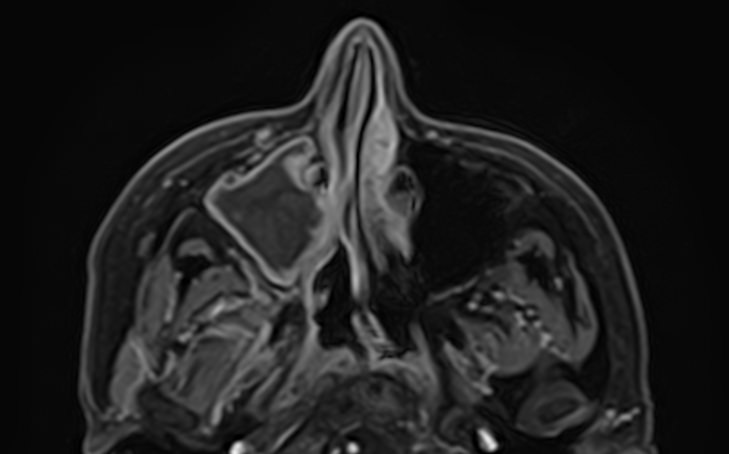

Чаще всего пазухи носа подвержены воспалительным процессам. В зависимости от поражения той или иной пазухи различают гайморит, фронтит, этмоидит, сфеноидит. Реже встречаются доброкачественные и злокачественные опухоли придаточных пазух носа.

МРТ является высокоинформативным способом визуализации данных анатомических областей. Метод позволяет диагностировать различные патологические процессы в области придаточных пазух носа. Кроме высокой информативности МРТ обладает такими преимуществами как достаточная быстрота, безболезненность и безопасность. Метод основан на использовании действия на ткани внешнего магнитного поля, при этом не применяется вредное рентгеновское излучение.

В случае подозрения на развитие опухолевого процесса в обязательном порядке показано введение контрастного вещества для лучшей визуализации патологических изменений в тканях. Степень и характер накопления контрастного препарата в органах и тканях позволяет различать патологические процессы, в том числе диагностировать опухоли на ранних стадиях. Так контрастирование помогает выявлять новообразования размером от 1 мм, что повышает шансы пациента на получение своевременного лечения и выздоровление.